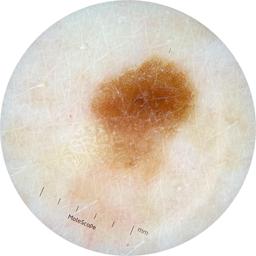

ISIC_8528385

MEL-SELF Trial, https://www.sydney.edu.au/medicine-health/our-research/research-centres/melself-project.html

image_type dermoscopic